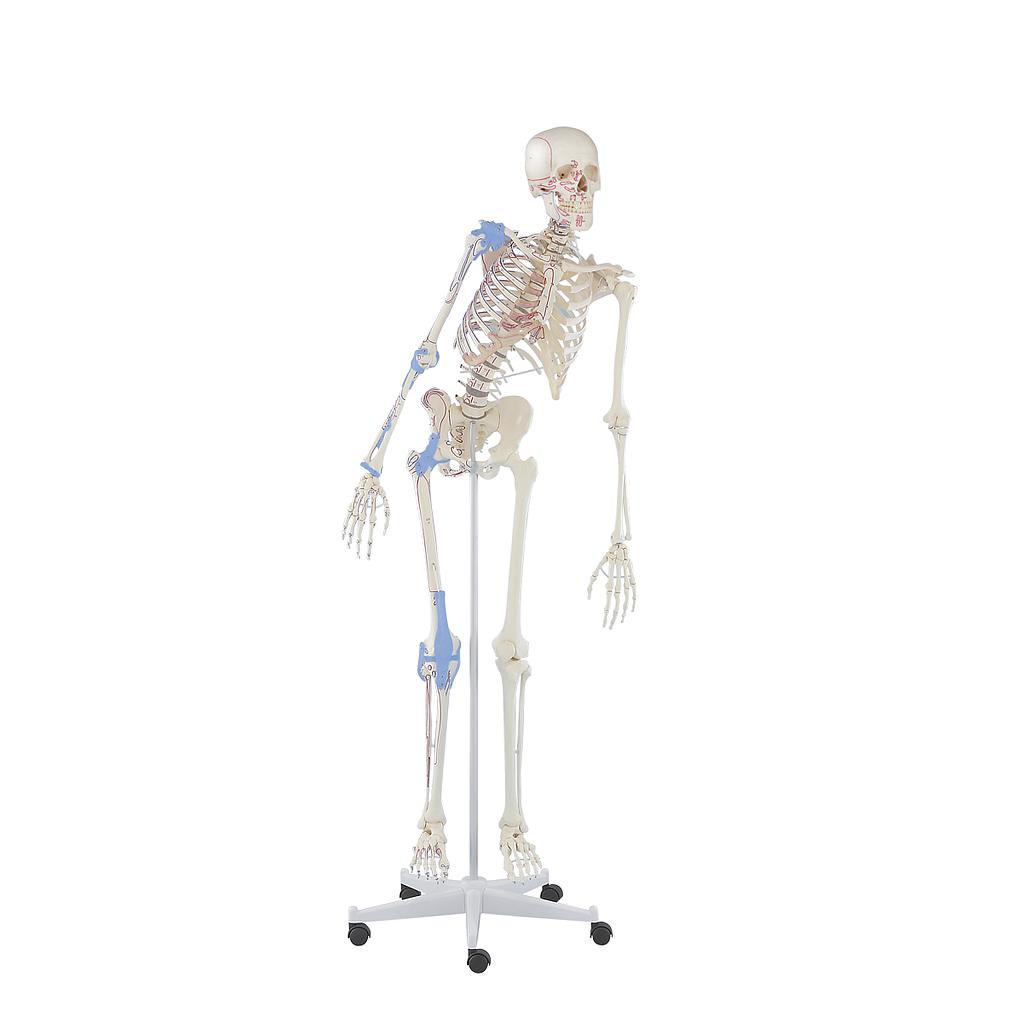

Squelette complet

Reproduction de première classe d'un squelette adulte masculin. Ce squelette est fabriqué selon nos normes de qualité strictes. Le montage stable et la structure robuste garantissent une qualité durable, même en utilisation intensive.